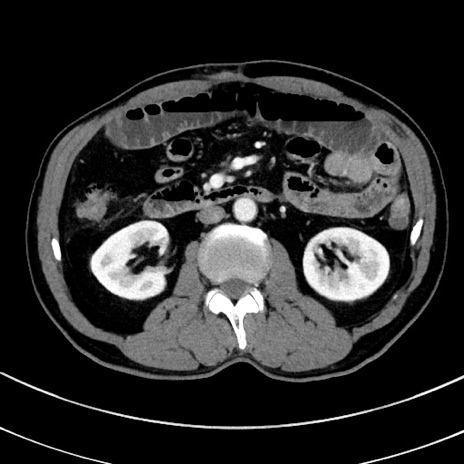

症例8(横断像)

【症例】 60歳代男性

【主訴】 黒色吐物

【現病歴】 4日前から嘔気自覚、2日前の朝食後にも嘔気あり、自分で手で嘔吐反射起こし嘔吐したところ血が混ざっていたため受診。

【既往歴】 5年前汎発性腹膜炎を伴う急性虫垂炎で手術、高血圧、前立腺肥大症、高脂血症

【身体所見】 腹部正中に手術癩痕あり 腹部平坦・軟圧痛なし膨満感あり

【データ】WBC 8400、CRP 4.54